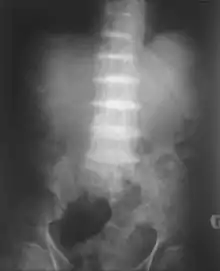

After the age of 30, people begin to develop pain in the weight-bearing joints of the spine, hips, and knees. The pain can be severe to the point that interferes with activities of daily living and may affect the ability to work. Joint-replacement surgery (hip and shoulder) is often necessary at a relatively young age.[1] In the longer term, the involvement of the spinal joints leads to reduced movement of the rib cage and can affect breathing.[1] Bone mineral density may be affected, increasing the risk of bone fractures, and rupture of tendons and muscles may occur.[1]